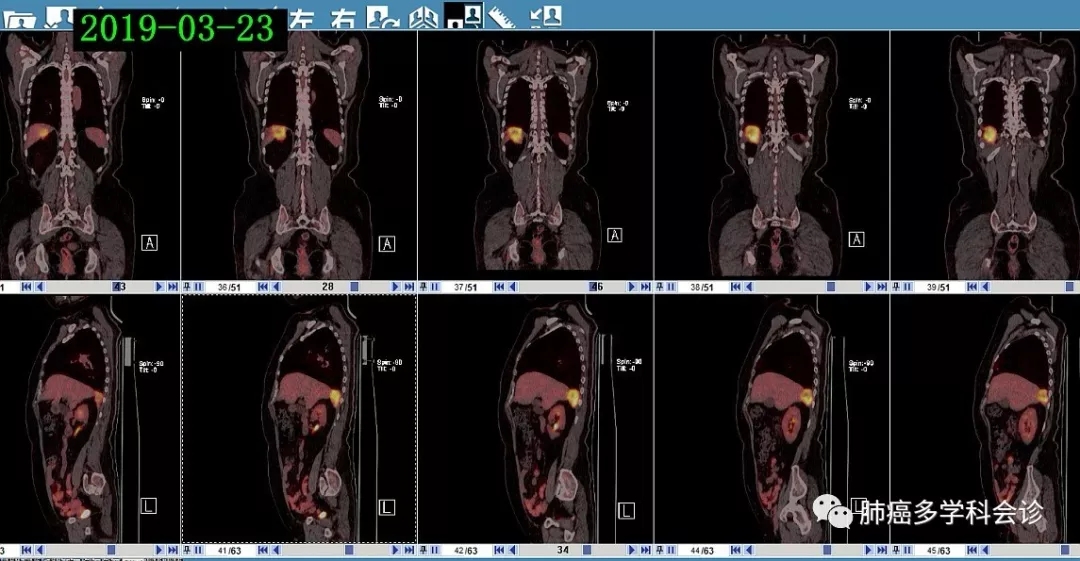

于术后20个月左右肿瘤复发,PET-CT(2019-03-23):右肺上叶支气管断端软组织影、代谢较活跃,考虑复发;膈肌右上份上方团块状软组织影代谢活跃,纵膈(2R区)及膈上前群肿大淋巴结代谢稍活跃,考虑转移。